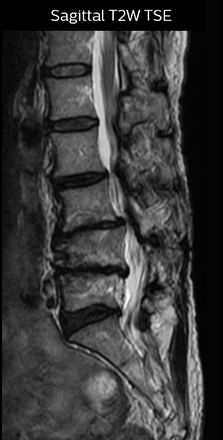

“For example, in sagittal images, when the presence of fat is observed in the intervertebral foramen, it suggests that there is a margin around the nerve. Similarly, the absence of fat indicates that the nerve is being compressed. So, we used to deduce nerve compression indirectly. With NerveVIEW, however, we can observe the condition of the nerves directly, regardless of the presence or absence of fat. We always prefer such direct observation of anatomy over having to make an inference about it.”

“Although symptoms of typical disc herniation and atypical hernia are very similar, the actual site of herniation is different. It is therefore important to characterize the nerve’s condition both inside and outside of the intervertebral foramina. “Conversely, if we see no abnormality in NerveVIEW, we can assume at least that there is no severe condition that requires surgery. Like this, it can help us avoid unnecessary surgery. NerveVIEW can have a tremendous impact in this way.”

“The intra-luminal signal of veins, especially around the intervertebral space, can be suppressed well with NerveVIEW. As a result, we can easily observe the detailed nerve structure around the posterior ganglion,” he says. “This is why we use 3D NerveVIEW for intraforaminal stenosis and extraforaminal stenosis/herniation (lateral disc herniation). On the other hand, if herniation is suspected to exist inside the dorsal root ganglion (DRG), balanced TFE or ProSet-FFE is applied. NerveVIEW is not suitable for evaluating the median type of herniation.” The SE-EPI DWI-based method for MR neurography works well for large FOV exams like whole-body MRI, but focal examination of nerves is often limited by the attainable spatial resolution (both inplane and slice direction) and geometric distortion. “3D NerveVIEW achieves higher in-plane resolution – close to our other routine spine sequences – and the source images can be used instead of adding a fat-suppressed T2-weighted sequence,” Tanji says.

“For both brachial and lumbar plexus, we are currently using a 230 mm FOV and voxels of about 1 x 1 x 2 mm acquired (1 x 1 x 1 mm reconstructed). This provides us a good representation of the nerves, even though this FOV is relatively small. Regarding the inplane resolution, we hope to be able to bring that down to 0.7 mm, similar to our typical 2D multislice T2W images,” says Tanji.